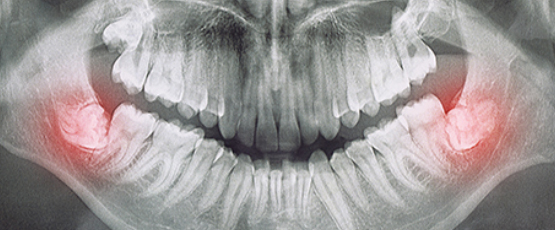

• 신경선까지 고려한 발치 기술

디지털 정밀 진단을 통해 신경선까지

고려한 사랑니 발치가 가능합니다.